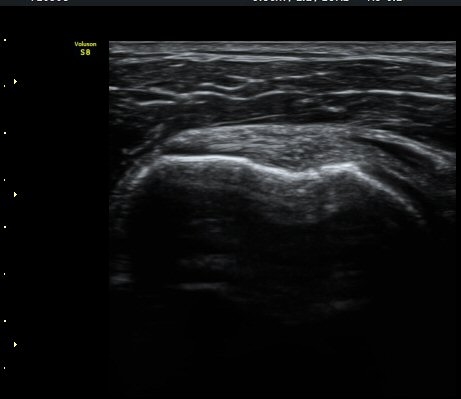

°Ë»ç»ó(±×¸² 7) ƯÀÌ ¼Ò°ßÀ» º¸ÀÌÁö ¾Ê´Â´Ù. ±Ø»ó°Ç Ⱦ´Ü¸é °Ë»ç»ó ±Ø»ó°ÇÀÇ ±ÙÀ§ºÎ¿¡¼­´Â

ƯÀÌ ¼Ò°ßÀ» º¸ÀÌÁö ¾ÊÀ¸³ª(±×¸² 8) ±Ø»ó°Ç ¸»´ÜºÎÀ§¿¡¼­ ´ë°áÀýÀÇ °ñ °áÇ̰ú ÇÇÁú°ñ ¿¬°á¼º